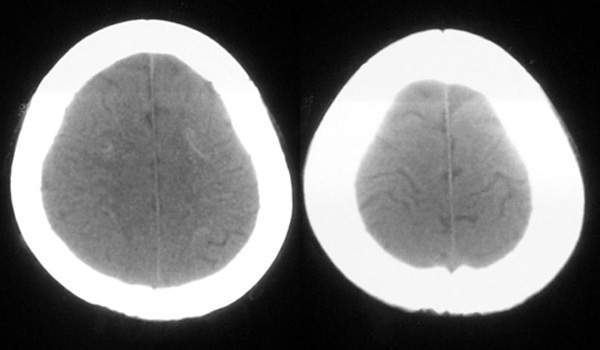

患者,女,49岁,头痛数年,有癫痫病史,无外伤史。

甲状旁腺低下:颅脑 ct 可见以基底节为中心的双侧对称性、多发性、多形性脑钙化的特点。除苍白球外,可广泛分布于壳核、尾状核、小脑齿状核、丘核、内囊及脑皮质、白质等处。